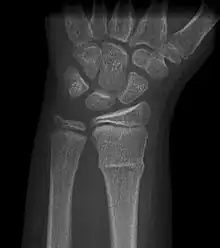

Buckle fracturs can be identified by performing a radiograph. The diagnosis of a torus fracture is made from both anterior/posterior and lateral projections. The typical features include:

- The buckling of cortical bone, which may appear as a small bulge or protuberance in the radius or ulna.

- The bone may have a slight angulation.[8]